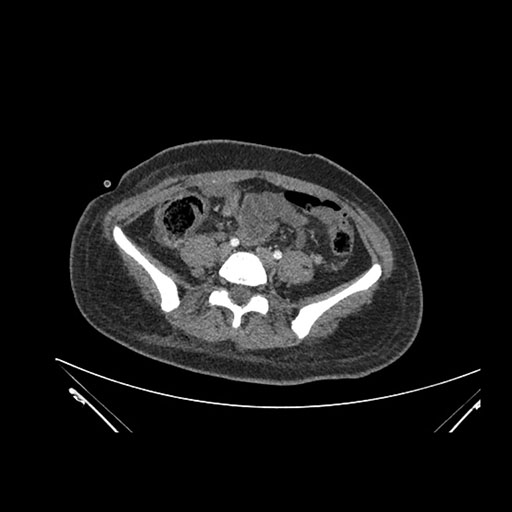

Imaging Analysis

Look through the patient's CT scan to identify any areas of concern for the necessary procedure.

Coronal Venous

Based on initial findings, which issue(s) would you be most concerned about?